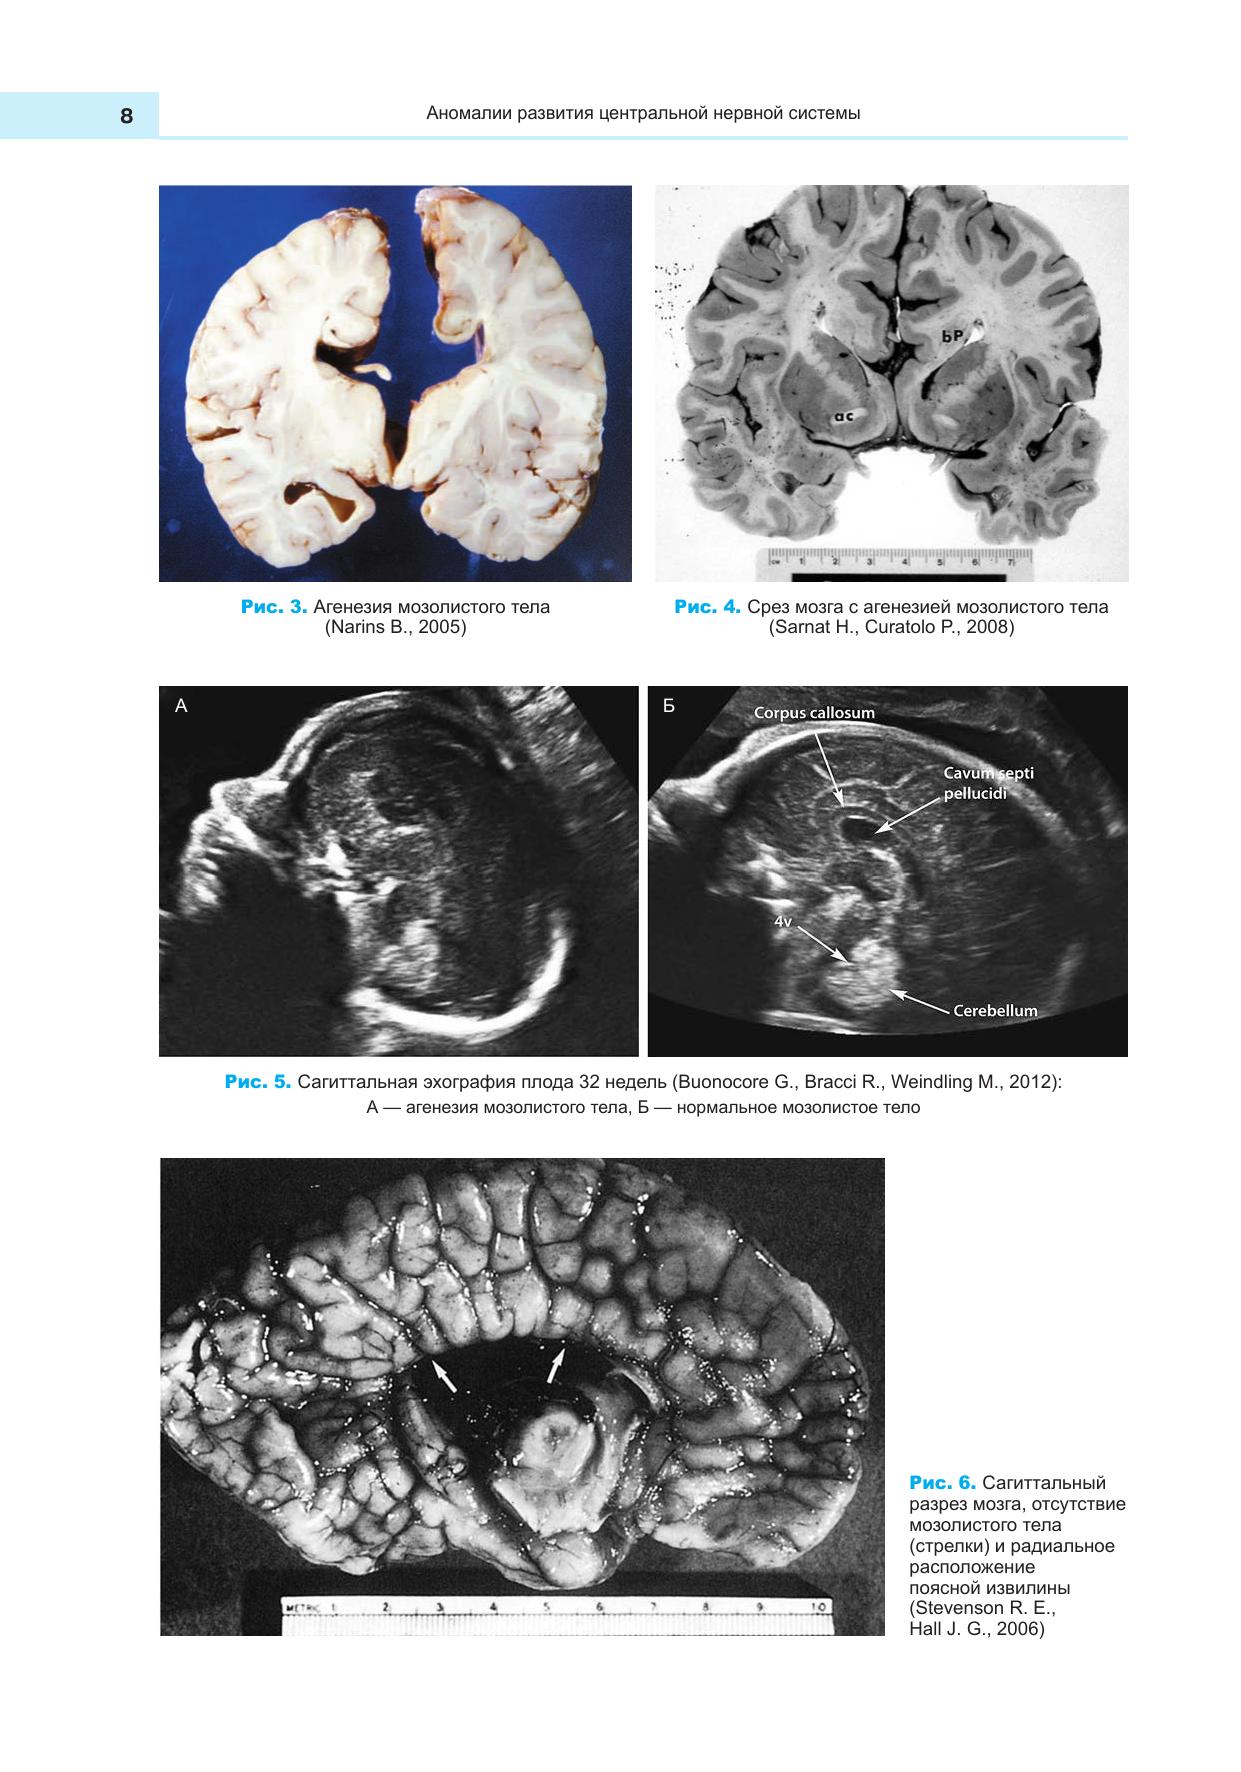

Пособие содержит краткое описание пороков и аномалий развития центральной нервной и сердечно-сосудистой систем человека, систематизированных на основе международной классификации пороков развития ВОЗ и международной статистической классификации болезней и причин, связанных со здоровьем. Пособие содержит большое количество иллюстративного материала. Учебное пособие предназначено для студентов вузов.